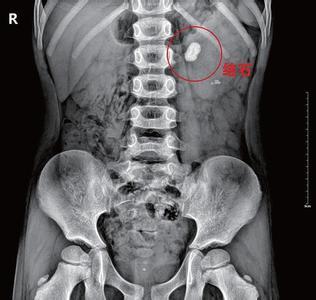

肾结石为泌尿系统常见病,多发病,男性发病多于女性,多发生于青壮年,左右侧的发病率无明显差异。40%~75%的肾结石患者有不同程度的腰痛。结石较大,移动度很小,表现为腰部酸胀不适,或在身体活动增加时有隐痛或钝痛。较小结石引发的绞痛,常骤然发生腰腹部刀割样剧烈疼痛,呈阵发性。